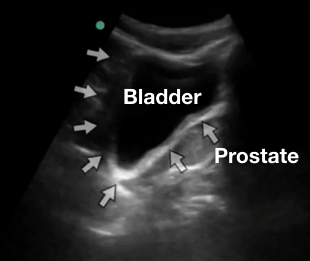

Pelvis

Liquide libre abdominal